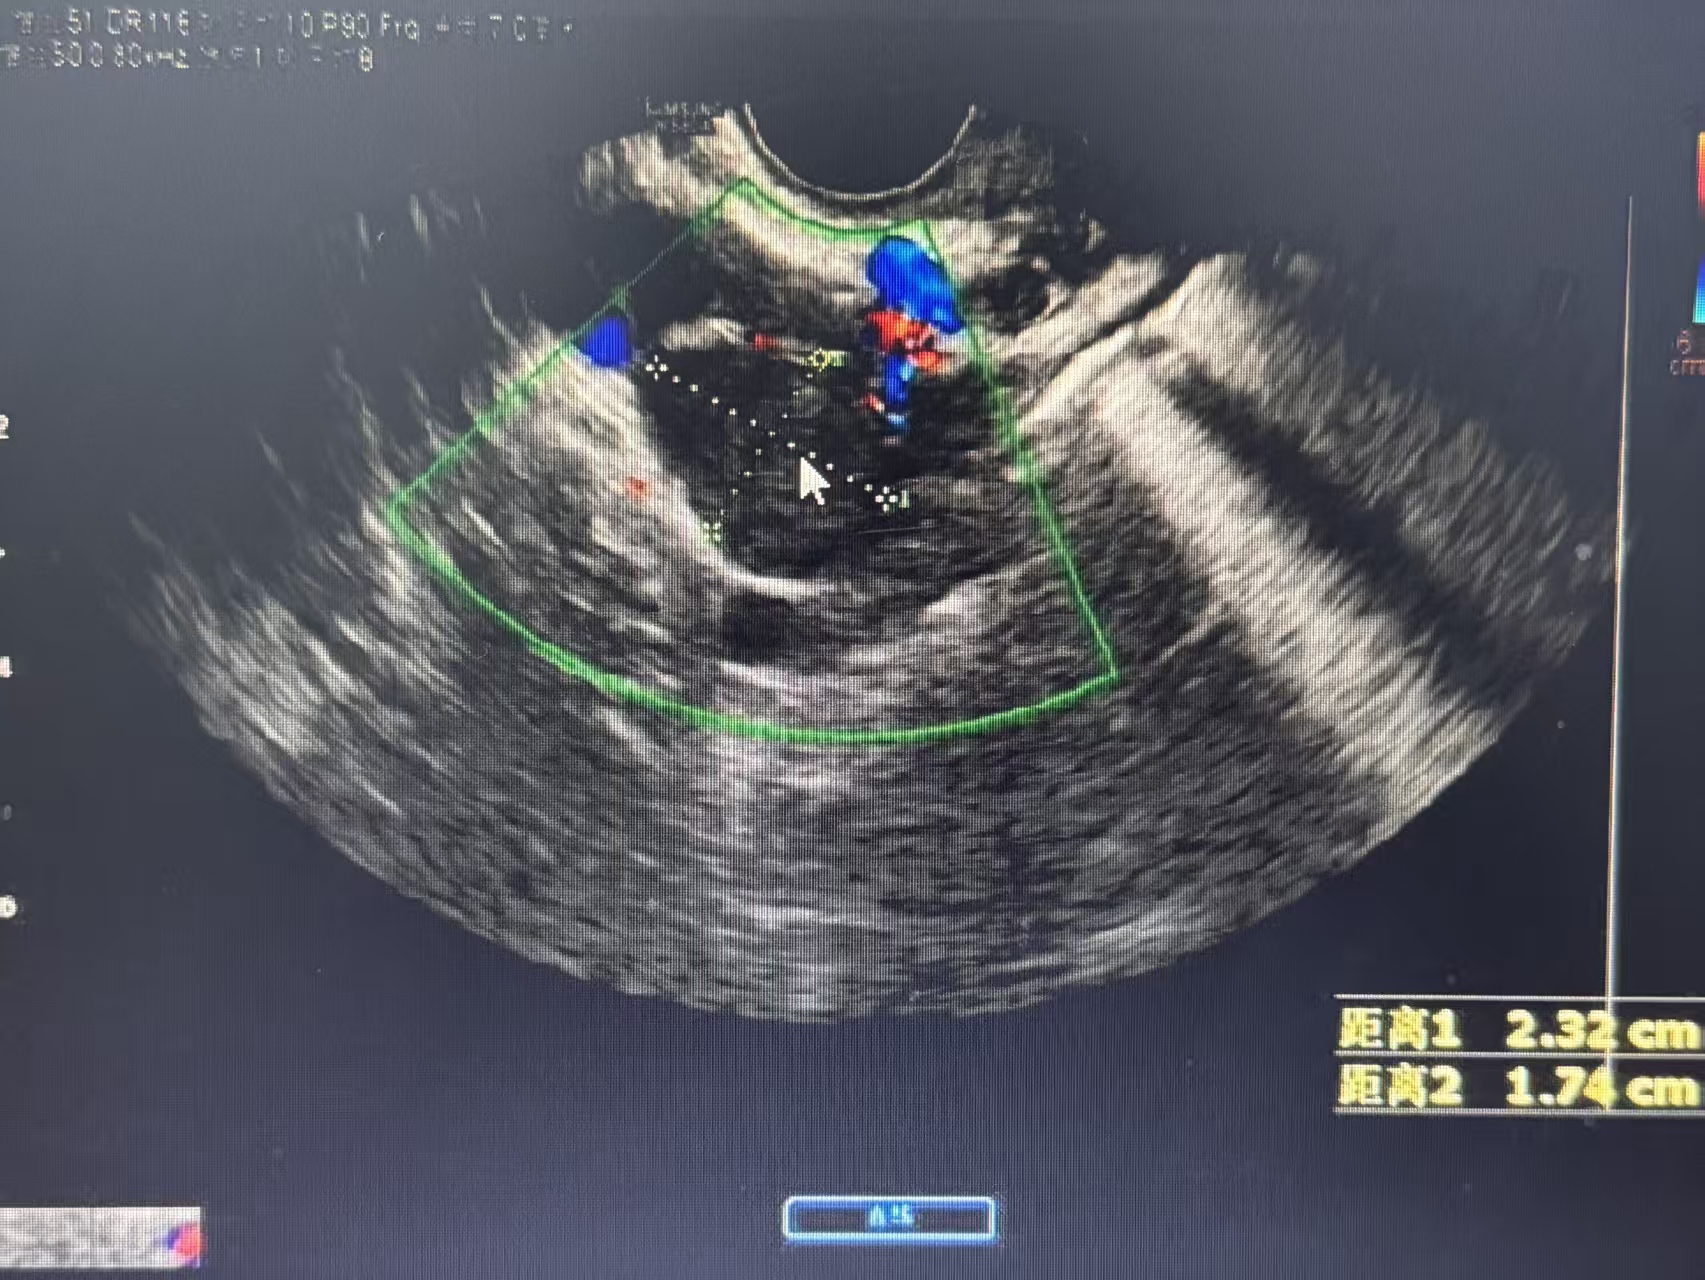

超声检查无辐射、无创、实时,能清晰显示囊肿的位置、大小、形态、内部结构和血流情况,宛如一位敏锐的侦探,为我们提供第一手证据。经阴道超声分辨率更高,是观察卵巢细节的利器。

3. 血流信号:通过彩色多普勒超声观察。良性囊肿通常血流信号稀少、规则。若实性部分或分隔上探及丰富、紊乱的血流信号,则提示生长活跃,需高度重视。